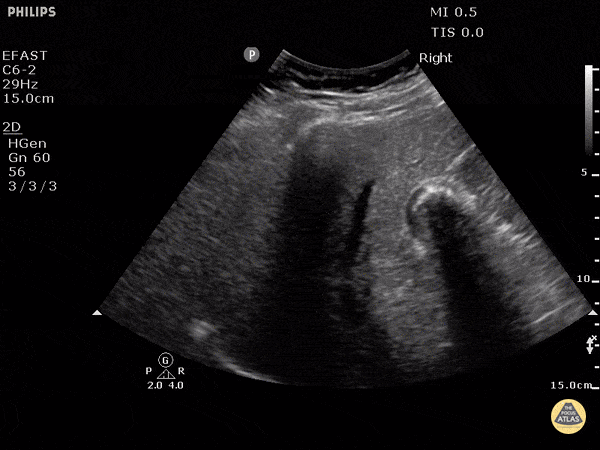

Biliary - Gallbladder Wall Echo Shadow (WES Sign)

Gallstones can be seen on the right side of the image with a hyperechoic front edge and posterior shadowing. Justin Bowra MBBS, FACEM, CCPU Emergency Physician, RNSH et al.